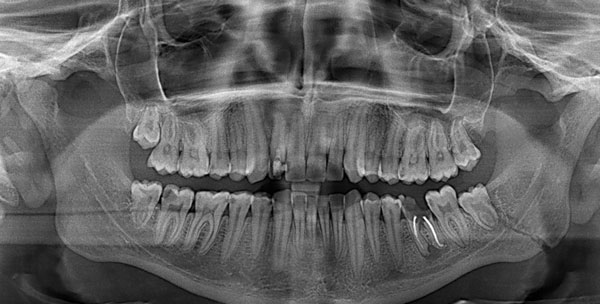

| Травма зубов | Отсутствует, присутствует | Стоматологическая помощь |

При обращении пациента в травматологический пункт в первую очередь проводится физикальный осмотр. При необходимости назначается рентгенографическое исследование. Если травмы мягких тканей сопровождаются повреждениями твердых тканей, таких как зубы, потребуется консультация специалистов. Дальнейшее лечение будет осуществляться челюстно-лицевым хирургом и стоматологом.